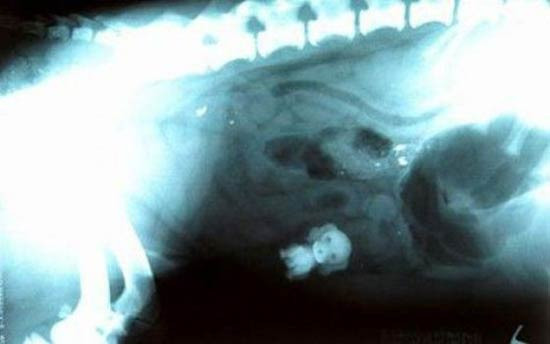

Köpeğin midesinden çıkana bak!